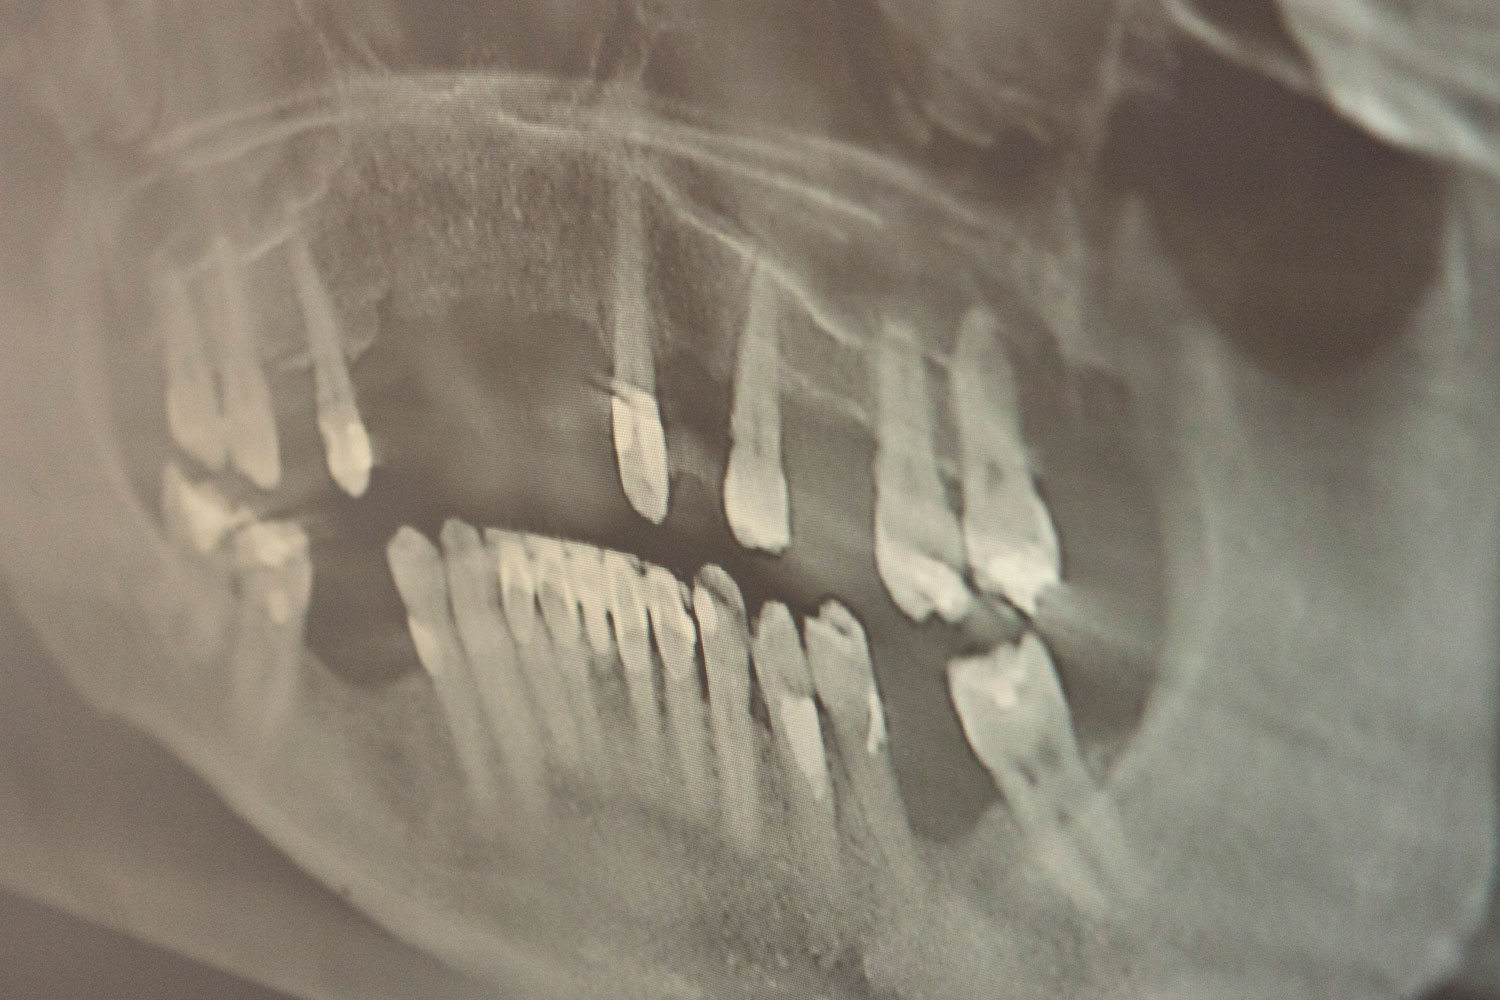

Die Aufgabe der Parodontologie ist die Prävention, Behandlung und Nachsorge von Zahnbetterkrankungen. Häufigste Form einer Zahnbetterkrankung ist die Parodontitis. Hierbei bildet sich der Alveolarknochen zurück, die Zahnfleischtaschen vertiefen sich, die Zahnwurzel findet insgesamt weniger Halt.

Begünstigende Faktoren für die Entstehung einer Parodontitis ist das Vorhandensein von Plaque (Zahnbelag), genetischen Faktoren, Rauchen und Stressfaktoren.

Die Therapie erfolgt durch Instruktion und Anpassung der Mundhygienemittel sowie einer perfekten Entfernung aller harten und weichen Zahnbeläge oberhalb und unterhalb des Zahnfleisches. Das Ziel der Parodontologie ist es, möglichst eine Schrumpfung des Zahnfleisches und den Abbau des Alveolarknochens zu verhindern.